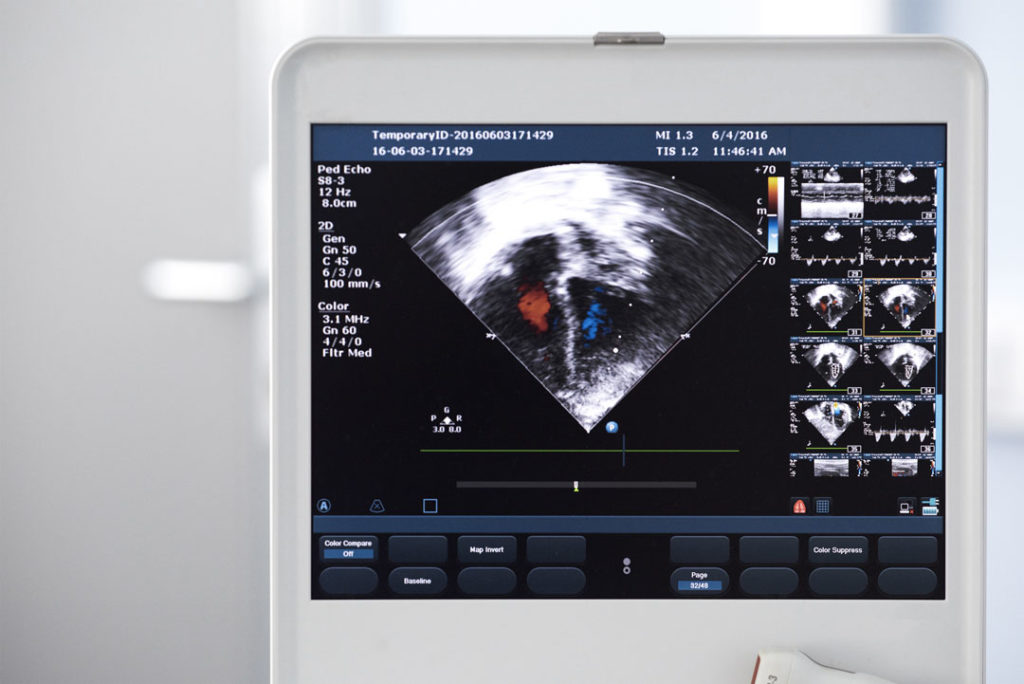

- Residência em Cardiologia e Ecocardiografia no Instituto Dante Pazzanese de Cardiologia, em 1992;